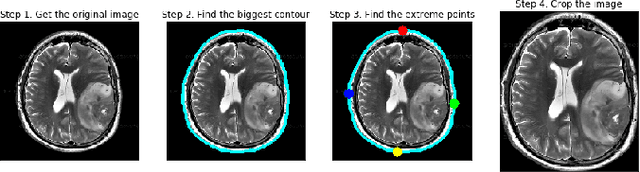

Abstract:Image processing concepts can visualize the different anatomy structure of the human body. Recent advancements in the field of deep learning have made it possible to detect the growth of cancerous tissue just by a patient's brain Magnetic Resonance Imaging (MRI) scans. These methods require very high accuracy and meager false negative rates to be of any practical use. This paper presents a Convolutional Neural Network (CNN) based transfer learning approach to classify the brain MRI scans into two classes using three pre-trained models. The performances of these models are compared with each other. Experimental results show that the Resnet-50 model achieves the highest accuracy and least false negative rates as 95% and zero respectively. It is followed by VGG-16 and Inception-V3 model with an accuracy of 90% and 55% respectively.